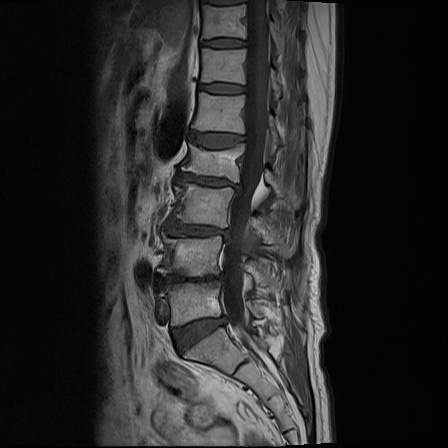

Ӵϲ ɿ ô ô 㸮 ٸ ̾ϴ. ϵ Ͻð ܻ 㸮 20⵿ ͽϴ. mri ˻ ɿ Ȳ ʹ ؼ Ȳ̶ ߽ϴ. ϻȰ ϰ 鼭 ½ϴ. ̴ ø鼭 Ͻô Ȳ ̷ ġ ص ȸ ϴ. δ Ҵµ, ù ȸԲ ˷ֽ ϰ β ϰ, ˷ֽ ü ƮĪ ϸ鼭 ȭǸ鼭 Ӵϲ ȸų ְ ǰ, β 鼭 ʴ β ؾϴ ŷο 1ϸ ijħ ڸ ǥ Ʈ ߽ϴ. ȸ ȭϽø鼭 Ϸ簡 ٸ ȸǽð 4ְ Ǿ Ǯ鼭 ¦ ҽϴ. ħ ȸ ȭϸ鼭 ڼ ü ƮĪ ϴ. ȥڼ Ͻʴϴ. ٳø鼭 ó Ͻ ʴϴ. ̾ ְ ̳ ߵ ʰ ϴ ȸԲ Ͻʴϴ. ʹ ϸ鼭 ϴ. Ȩ - ϱ ٴ Ȳ MRIԴϴ. |